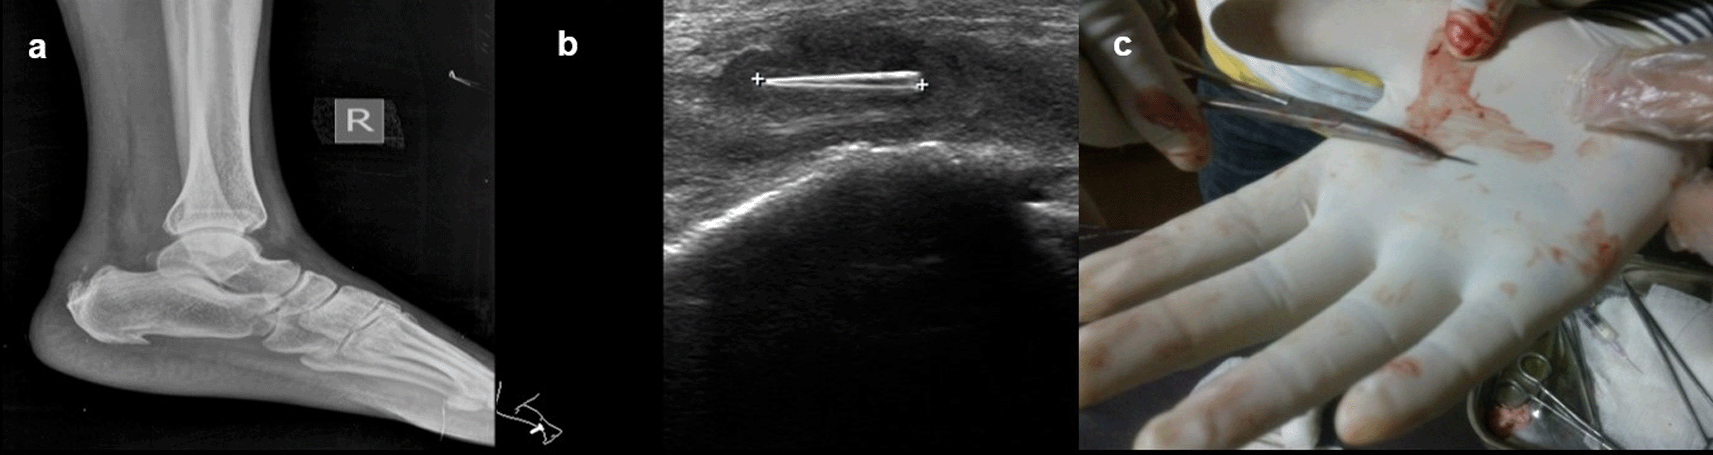

Case 7: A 40-year-old male presented with a complaint of pain in the right heel region for two months. On examination, he had mild, hard swelling on the posterior part of the ankle. A radiograph of the lateral view of the right foot revealed there was evidence of calcific tendinitis of the Achilles tendon with thickening of the Kager fat pad and fat stranding. USG revealed that a well-defined thorn visualized in the Achilles tendon with associated surrounding tendinitis and increased fat echogenicity. USG-guided thorn removal was performed.

On ultrasound, all foreign bodies in soft tissue are initially hyperechoic. Sonography is important for the correct localization of all kinds of soft tissue foreign bodies and the detection of non-radiopaque foreign bodies. Accurate localization can help minimize surgical exploration and can also direct the percutaneous removal of a foreign body11 (Figure 7a,b)

USG revealed that a well-defined thorn visualized in the Achilles tendon with associated changes of tendinitis (b). Thorn removed under ultrasound guidance (c).